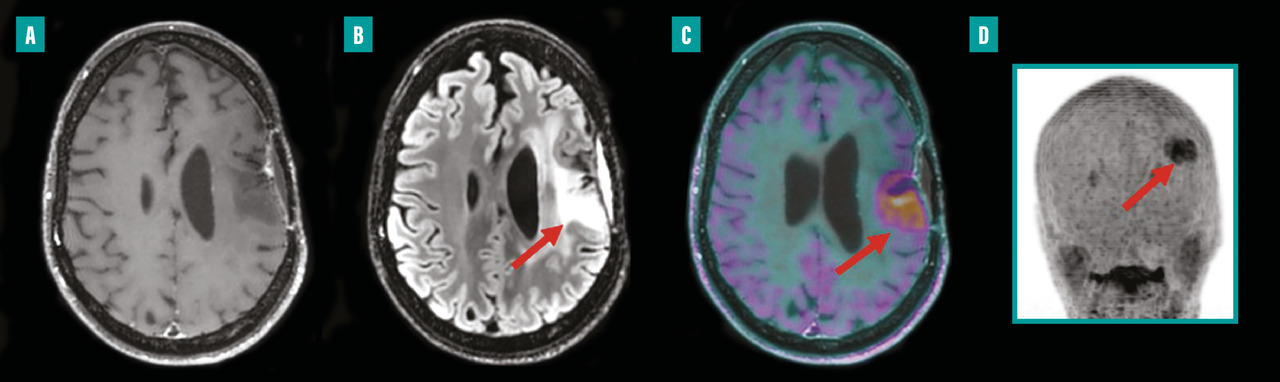

Depuis environ une décennie, des systèmes hybrides alliant TEP et imagerie par résonance magnétique (IRM) sont disponibles en milieu clinique. La TEP-IRM présente l’avantage d’exposer les patients à moins de radiations que la TEP, ce qui est particulièrement bénéfique pour les enfants ou les personnes nécessitant des examens répétés dans le cadre de leur traitement. L’intégration de l’IRM améliore considérablement l’analyse des tissus mous et assure une correspondance spatiale parfaite avec les anomalies fonctionnelles détectées par la TEP. Grâce à sa haute résolution, la TEP-IRM permet d’examiner avec précision les petites structures et de détecter les changements subtils dans les images au cours du traitement. En oncologie, la TEP-IRM est principalement utilisée pour les patients atteints de cancers pelviens (gynécologiques et de la prostate) ainsi que pour les cancers ORL et en neuro-oncologie (fig. 1).9

La médecine nucléaire, depuis ses débuts, a joué un rôle non seulement en imagerie mais aussi en thérapie, notamment grâce à la radiothérapie interne vectorisée (RIV). L’iode 131, utilisé depuis longtemps pour traiter les troubles thyroïdiens, illustre bien cette dimension thérapeutique fondamentale de la discipline. Ce traitement a introduit le concept de théranostique, qui consiste à visualiser précisément la maladie avant de la traiter et ainsi à sélectionner les patients avec le phénotype le plus adapté (ceux avec la plus forte fixation) pour maximiser l’efficacité thérapeutique. Actuellement, la RIV est également appliquée dans le traitement des tumeurs neuro-endocrines et, depuis peu, dans le cancer de la prostate. En effet, en 2023, Pluvicto (lutécium [177Lu] vipivotide tétraxétan) a été approuvé pour le traitement du cancer de la prostate métastatique, résistant à la castration après échec du traitement par hormonothérapie et chimiothérapie (fig. 2).15 Les recherches actuelles examinent l’intégration de la RIV avec des thérapies ciblées et étudient son utilisation en première ligne de traitement.